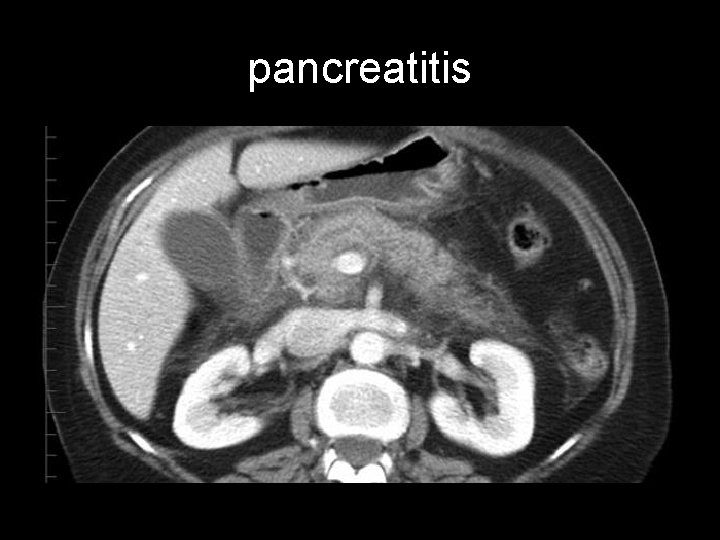

And…. If Murphy - - or the gallbladder is normal ? Differential diagnosis for acute cholecystitis includes: • • • choledocholithiasis pancreatitis peptic ulcer disease acute hepatitis liver abscess

pancreatitis